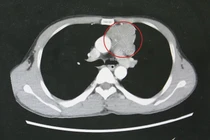

Quá trình chẩn đoán, qua chụp cắt lớp vi tính ổ bụng có hình ảnh khối u dạng đặc chiếm gần hết ổ bụng chủ yếu vùng bụng bên phải, chưa xâm lấn mạch máu lớn. Trên nội soi đường tiêu hoá thì khối u từ ngoài đẩy vào lòng đại tràng lên.

Khối u lớn khoang sau phúc mạc cạnh trước thận phải kích thước 233x191x141mm, bờ gọn, lan sang khoang cạnh trước thận trái, đè ép niệu quản phải gây giãn nhẹ đài bể thận phải, ngấm thuốc sau tiêm - Ảnh BVCC